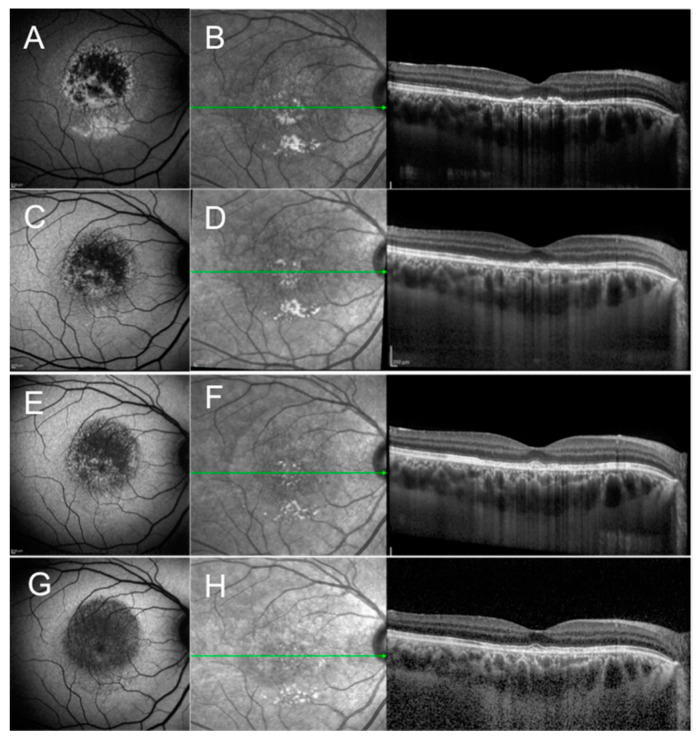

The disease is self-limiting and on average it takes 4 months (range 1–7 months) for the vision to recover and recurrences are rare [10,11]. OCT in the early phase may show a detached macula, with possible bacillary layer detachment, disruption of the outer retinal layers, and usually an intact external limiting membrane (ELM) (Figure 1). Later in the disease course, outer retinal layers mostly recover accompanied by vision improvement. Focal areas of either RPE thickening and/or RPE attenuation develop, consistent with choroidal hypo- and/or hyper-transmission on OCT, respectively.

Figure 1.

Fundus autofluorescence (FAF) and optical coherence tomography (OCT) scan of a case of acute idiopathic maculopathy of the right eye at presentation (A,B), 4 weeks after presentation (C,D), 8 weeks after presentation (E,F), and 12 weeks (G,H) after presentation. (A) FAF shows a predominant hypoautofluorescent signal surrounded by a hyperautofluorescent signal (Pattern 1 of the proposed disease Stage 1); (B) OCT shows disruption of the retinal pigment epithelium (RPE) and outer retinal layers with increased choroidal transmission; (C–H) Subsequent FAF and OCT scan during follow-up show decreasing intensity of the hypoautofluorescent signal and gradual improvement of the integrity of RPE and outer retinal layers, respectively. (G) Two years after presentation, FAF shows homogeneously decreased FAF (Pattern 4 of the proposed disease Stage 4).